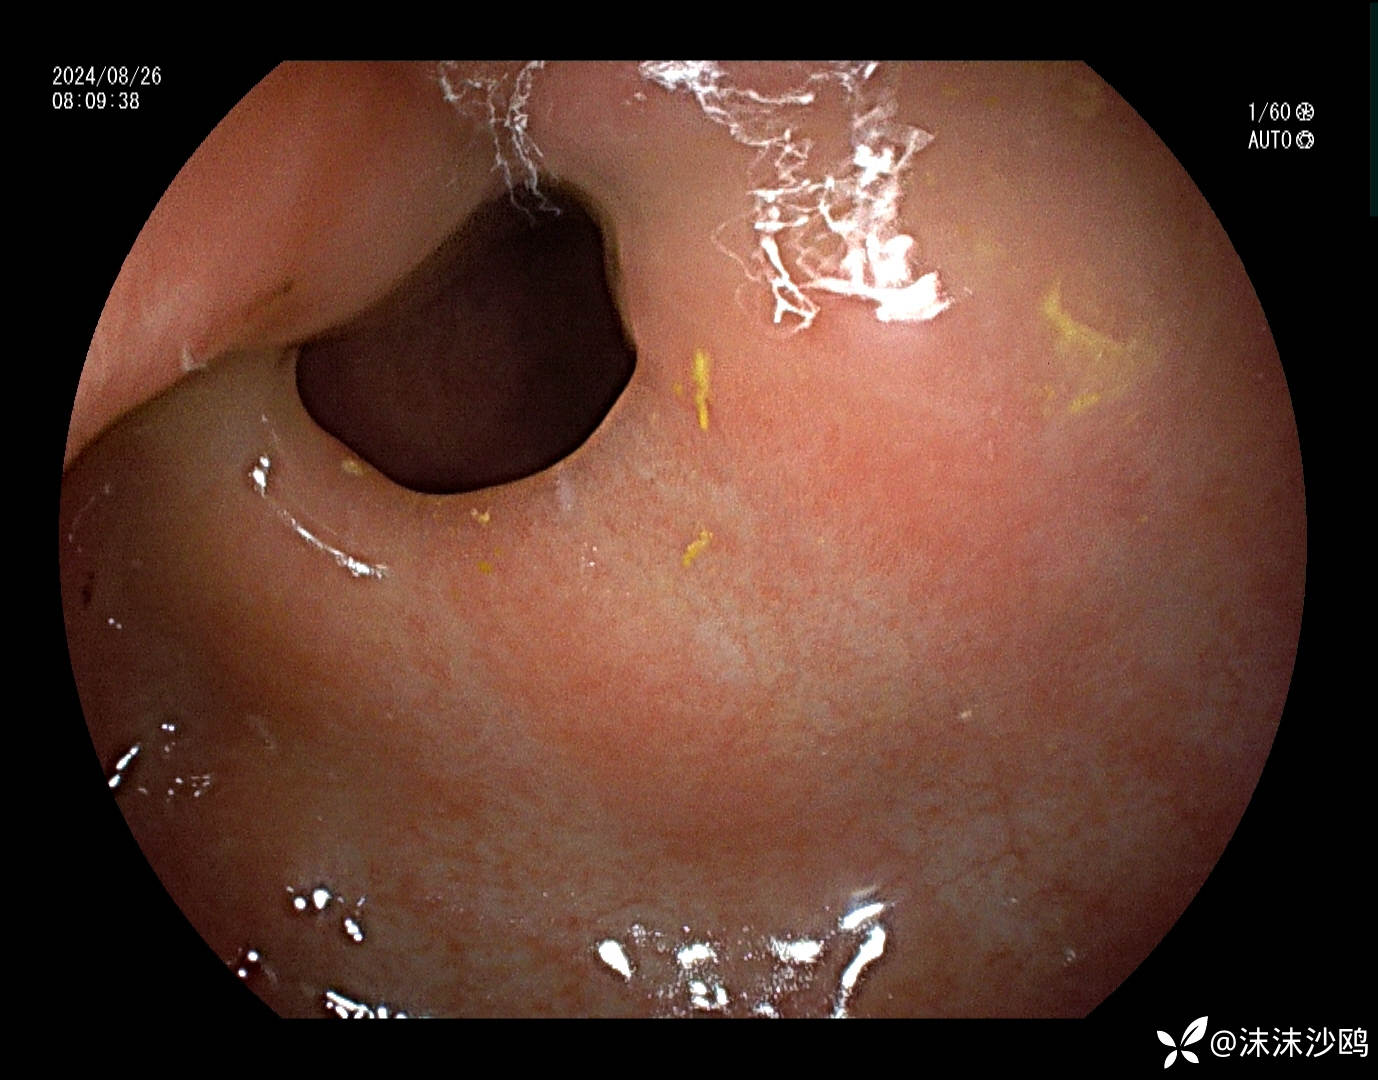

胃窦病变,小弯溃疡,幽门前区狭窄,假幽门形成。

真幽门

球部